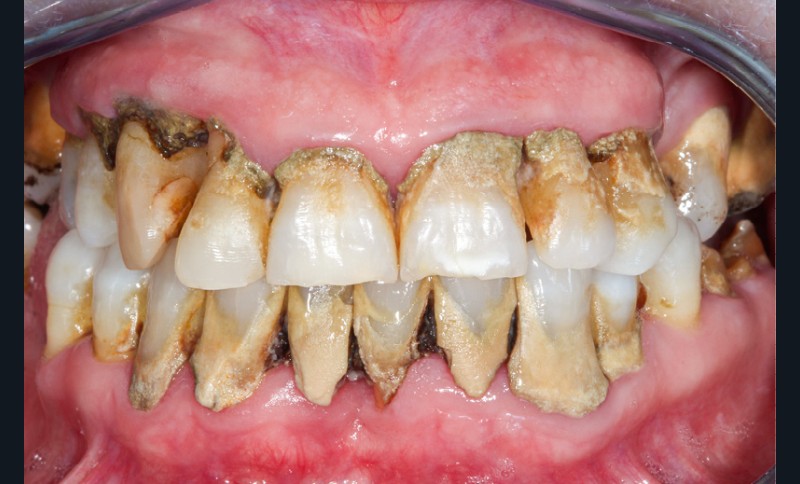

• Extrinsèques : liées aux colorations de surface (tabac, café, thé, vin rouge, alimentation, tartre ou plaque bactérienne) (fig. 4).